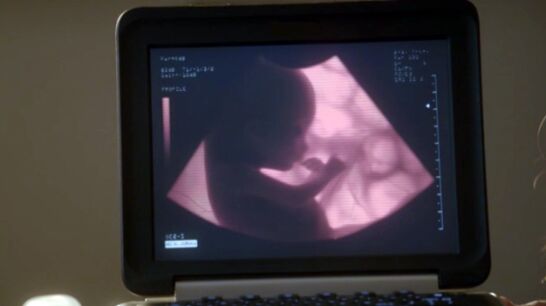

Molly se derrumba y Sam está de acuerdo en hacerle una ecografía para tratar de averiguar más cosas sobre su misterioso embarazo, pero en un lugar lejos de la ISEA. Tras hacerle la ecografía, su compañera se cerciora de que está embaraza y de 14 semanas, algo que no entiende Molly ya que en ese periodo estuvo sola a bordo del Seraphim.